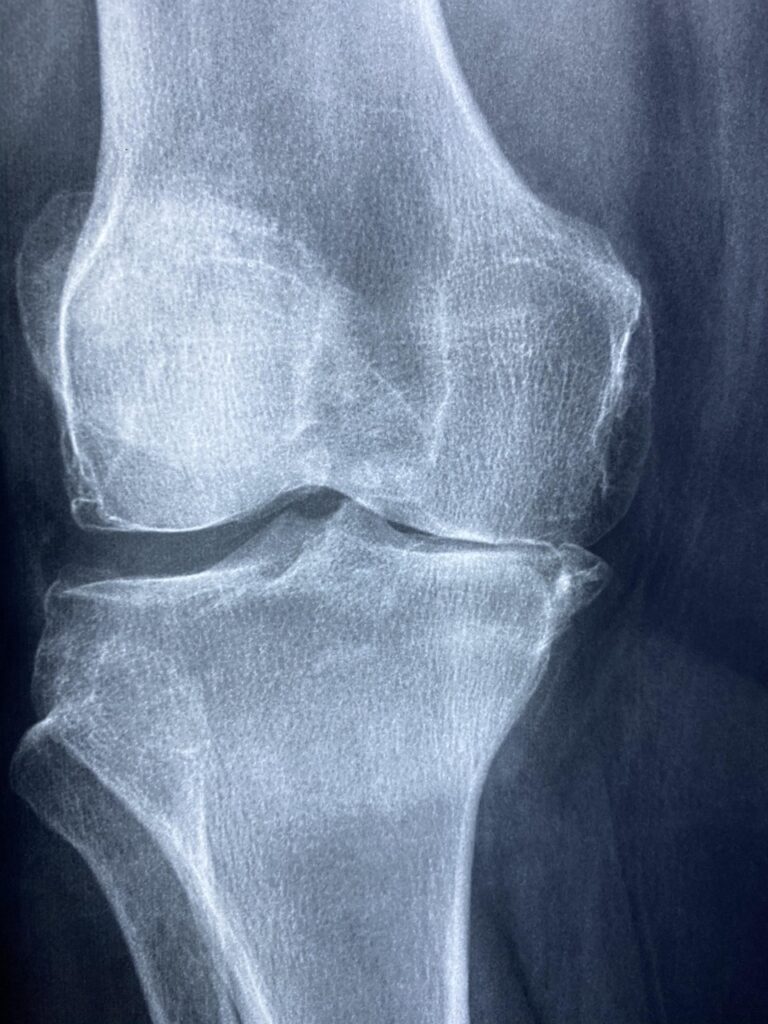

変形性膝関節症は、膝関節の軟骨が劣化し、痛みや運動制限を引き起こす病気です。

年齢や体重、遺伝的要因などが影響し、特に中高年層に多く見られます。

症状が進行すると、日常生活に支障をきたすこともありますが、必ずしも手術が必要なわけではありません。